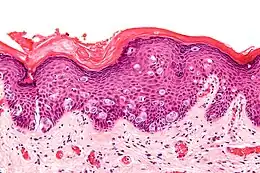

Coupe histologique de maladie de Paget extramammaire, coloration H&E.

L'examen histologique[7] d'une biopsie confirme (ou permet, en l'absence de reconnaissance initiale de la lésion) le diagnostic. L'aspect retrouvé est identique à celui de la maladie de Paget du sein.